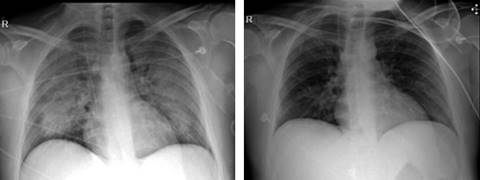

Hombre de 39 años, originario y residente de la Ciudad de México, licenciado en Administración. Con antecedente de neumopatía crónica por uso y abuso del tabaco, con un índice tabáquico de 20.7, además de dislipidemia de reciente diagnóstico en tratamiento con fenofibrato 250 mg vía oral cada 12 horas. Inicia su padecimiento el día 21 de junio del año en curso, posterior a exposición con líquido limpiador de calzado a base de heptano, isobutano, petróleo de fracción alifática ligera y propano; con un tiempo de contacto de dos horas, mientras se encontraba en un sitio con mala ventilación. Dos horas posteriores a la exposición inició con tos seca intermitente, progresando a disnea de pequeños esfuerzos, dolor torácico opresivo que se exacerbaba a la inspiración, motivo por el cual acudió a valoración a una unidad médica en donde se le inició abordaje diagnóstico con toma de radiografía de tórax, laboratorios y gasometría, encontrándose con datos sugestivos de neumonitis química; se inició manejo con esteroides intravenosos y broncodilatadores a dosis no especificada, se egresó a domicilio a petición del paciente. Veinticuatro horas posteriores a su egreso persistía con la misma sintomatología, por lo que acude al Servicio de Urgencias del Hospital Ángeles del Pedregal. A su ingreso se encontraba taquicárdico y con taquipnea con tensión arterial de 130/80 mmHg, afebril, saturación de oxígeno de 88% al aire ambiente. Inicialmente se tomó gasometría arterial con datos de alcalosis respiratoria crónica, mejorando la saturación con aplicación de oxígeno suplementario por puntas nasales llegando hasta 94% de saturación. A la exploración física faringe con hiperémica, tórax simétrico, con adecuados movimientos respiratorios, a la auscultación con ruidos respiratorios disminuidos de predominio en hemitórax izquierdo, vibraciones vocales disminuidas en ambos hemitórax, sin estertores o sibilancias, así como taquicardia de 120 por minuto; resto de la exploración sin alteraciones. Se solicitó tomografía simple de tórax (Figura 1), evidenciándose patrón alveolar central y difuso en lóbulos superiores, lóbulo medio, segmento lingular, segmento superior y segmento medial de ambos lóbulos inferiores con lo que se hizo el diagnóstico de neumonitis. Con estas evidencias y de acuerdo con su condición clínica se decidió su ingreso a la Unidad de Terapia Intensiva, con diagnóstico de neumonitis y quemadura química de la vía aérea, clasificándose como SOFA 2 de puntos, con una mortalidad de 6 al 8%. Se tomó electrocardiograma el cual mostró ritmo sinusal y sin datos de dilatación de cavidades y/o presencia de arritmias; los laboratorios con leucocitosis a expensas de neutrófilos, proteína C reactiva 86.57 mg/L, VSG 1 mm/hora, procalcitonina 11.87 ng/mL, glucosa 122 mg/dL, sin alteración a la función renal en niveles séricos. El tratamiento inicial fue a base de salbutamol/ipratropio 250 μg cada ocho horas, budesónida 800 μg cada seis horas, metilprednisolona un g cada 24 horas por tres días, meropenem un g cada ocho horas y claritromicina 500 mg cada 12 horas. Durante sus primeras 24 horas de estancia en la unidad, continuaba con persistencia de taquipnea (frecuencia respiratoria [FR] 35 respiraciones/min), decidiéndose manejo avanzado de la vía aérea, manteniéndose con ventilación mecánica asistida por 96 horas, en modo controlado por volumen (FR 14, VC 600, sensibilidad 2.1, PEEP 10), con parámetros de distensibilidad estática de 125 y distensibilidad dinámica 44.5. Por mejoría de imagen radiográfica y menor dependencia a la VMA, se realizó extubación sin presentar complicaciones, manteniendo adecuada saturación con puntas de alto flujo. Se muestra la progresión radiográfica (Figura 2) en la cual se evidencia mejoría de la radiopacidad generalizada en el parénquima pulmonar.

Figura 2: Progresión en radiografía de tórax (izquierda al ingreso, derecha el día del egreso), evidencia de mejoría de la radiopacidad generalizada en el parénquima pulmonar.